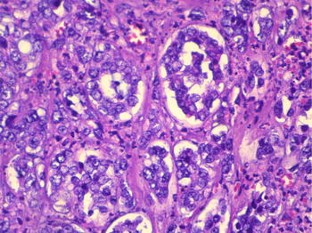

Fig. 1